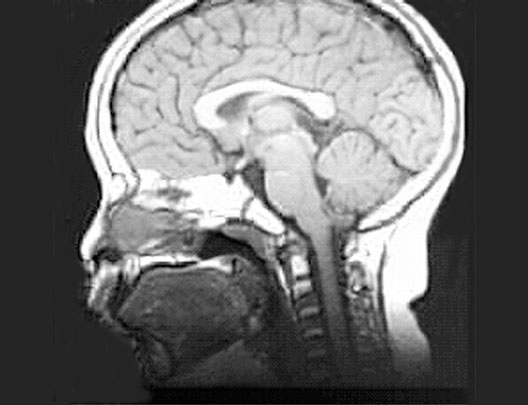

Radiology Images

Head MRI

Roll mouse over image to display labels.

1. Nasopharynx

2. Nasal Septum

3. Hard Palate

4. Tongue

5. Oropharynx

6. Laryngopharynx